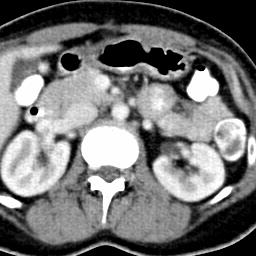

Due to the constraints of the imaging device and high cost in operation time, computer tomography (CT) scans are usually acquired with low intra-slice resolution. Improving the intra-slice resolution is beneficial to the disease diagnosis for both human experts and computer-aided systems. To this end, this paper builds a novel medical slice synthesis to increase the between-slice resolution. Considering that the ground-truth intermediate medical slices are always absent in clinical practice, we introduce the incremental cross-view mutual distillation strategy to accomplish this task in the self-supervised learning manner. Specifically, we model this problem from three different views: slice-wise interpolation from axial view and pixel-wise interpolation from coronal and sagittal views. Under this circumstance, the models learned from different views can distill valuable knowledge to guide the learning processes of each other. We can repeat this process to make the models synthesize intermediate slice data with increasing inter-slice resolution. To demonstrate the effectiveness of the proposed approach, we conduct comprehensive experiments on a large-scale CT dataset. Quantitative and qualitative comparison results show that our method outperforms state-of-the-art algorithms by clear margins.